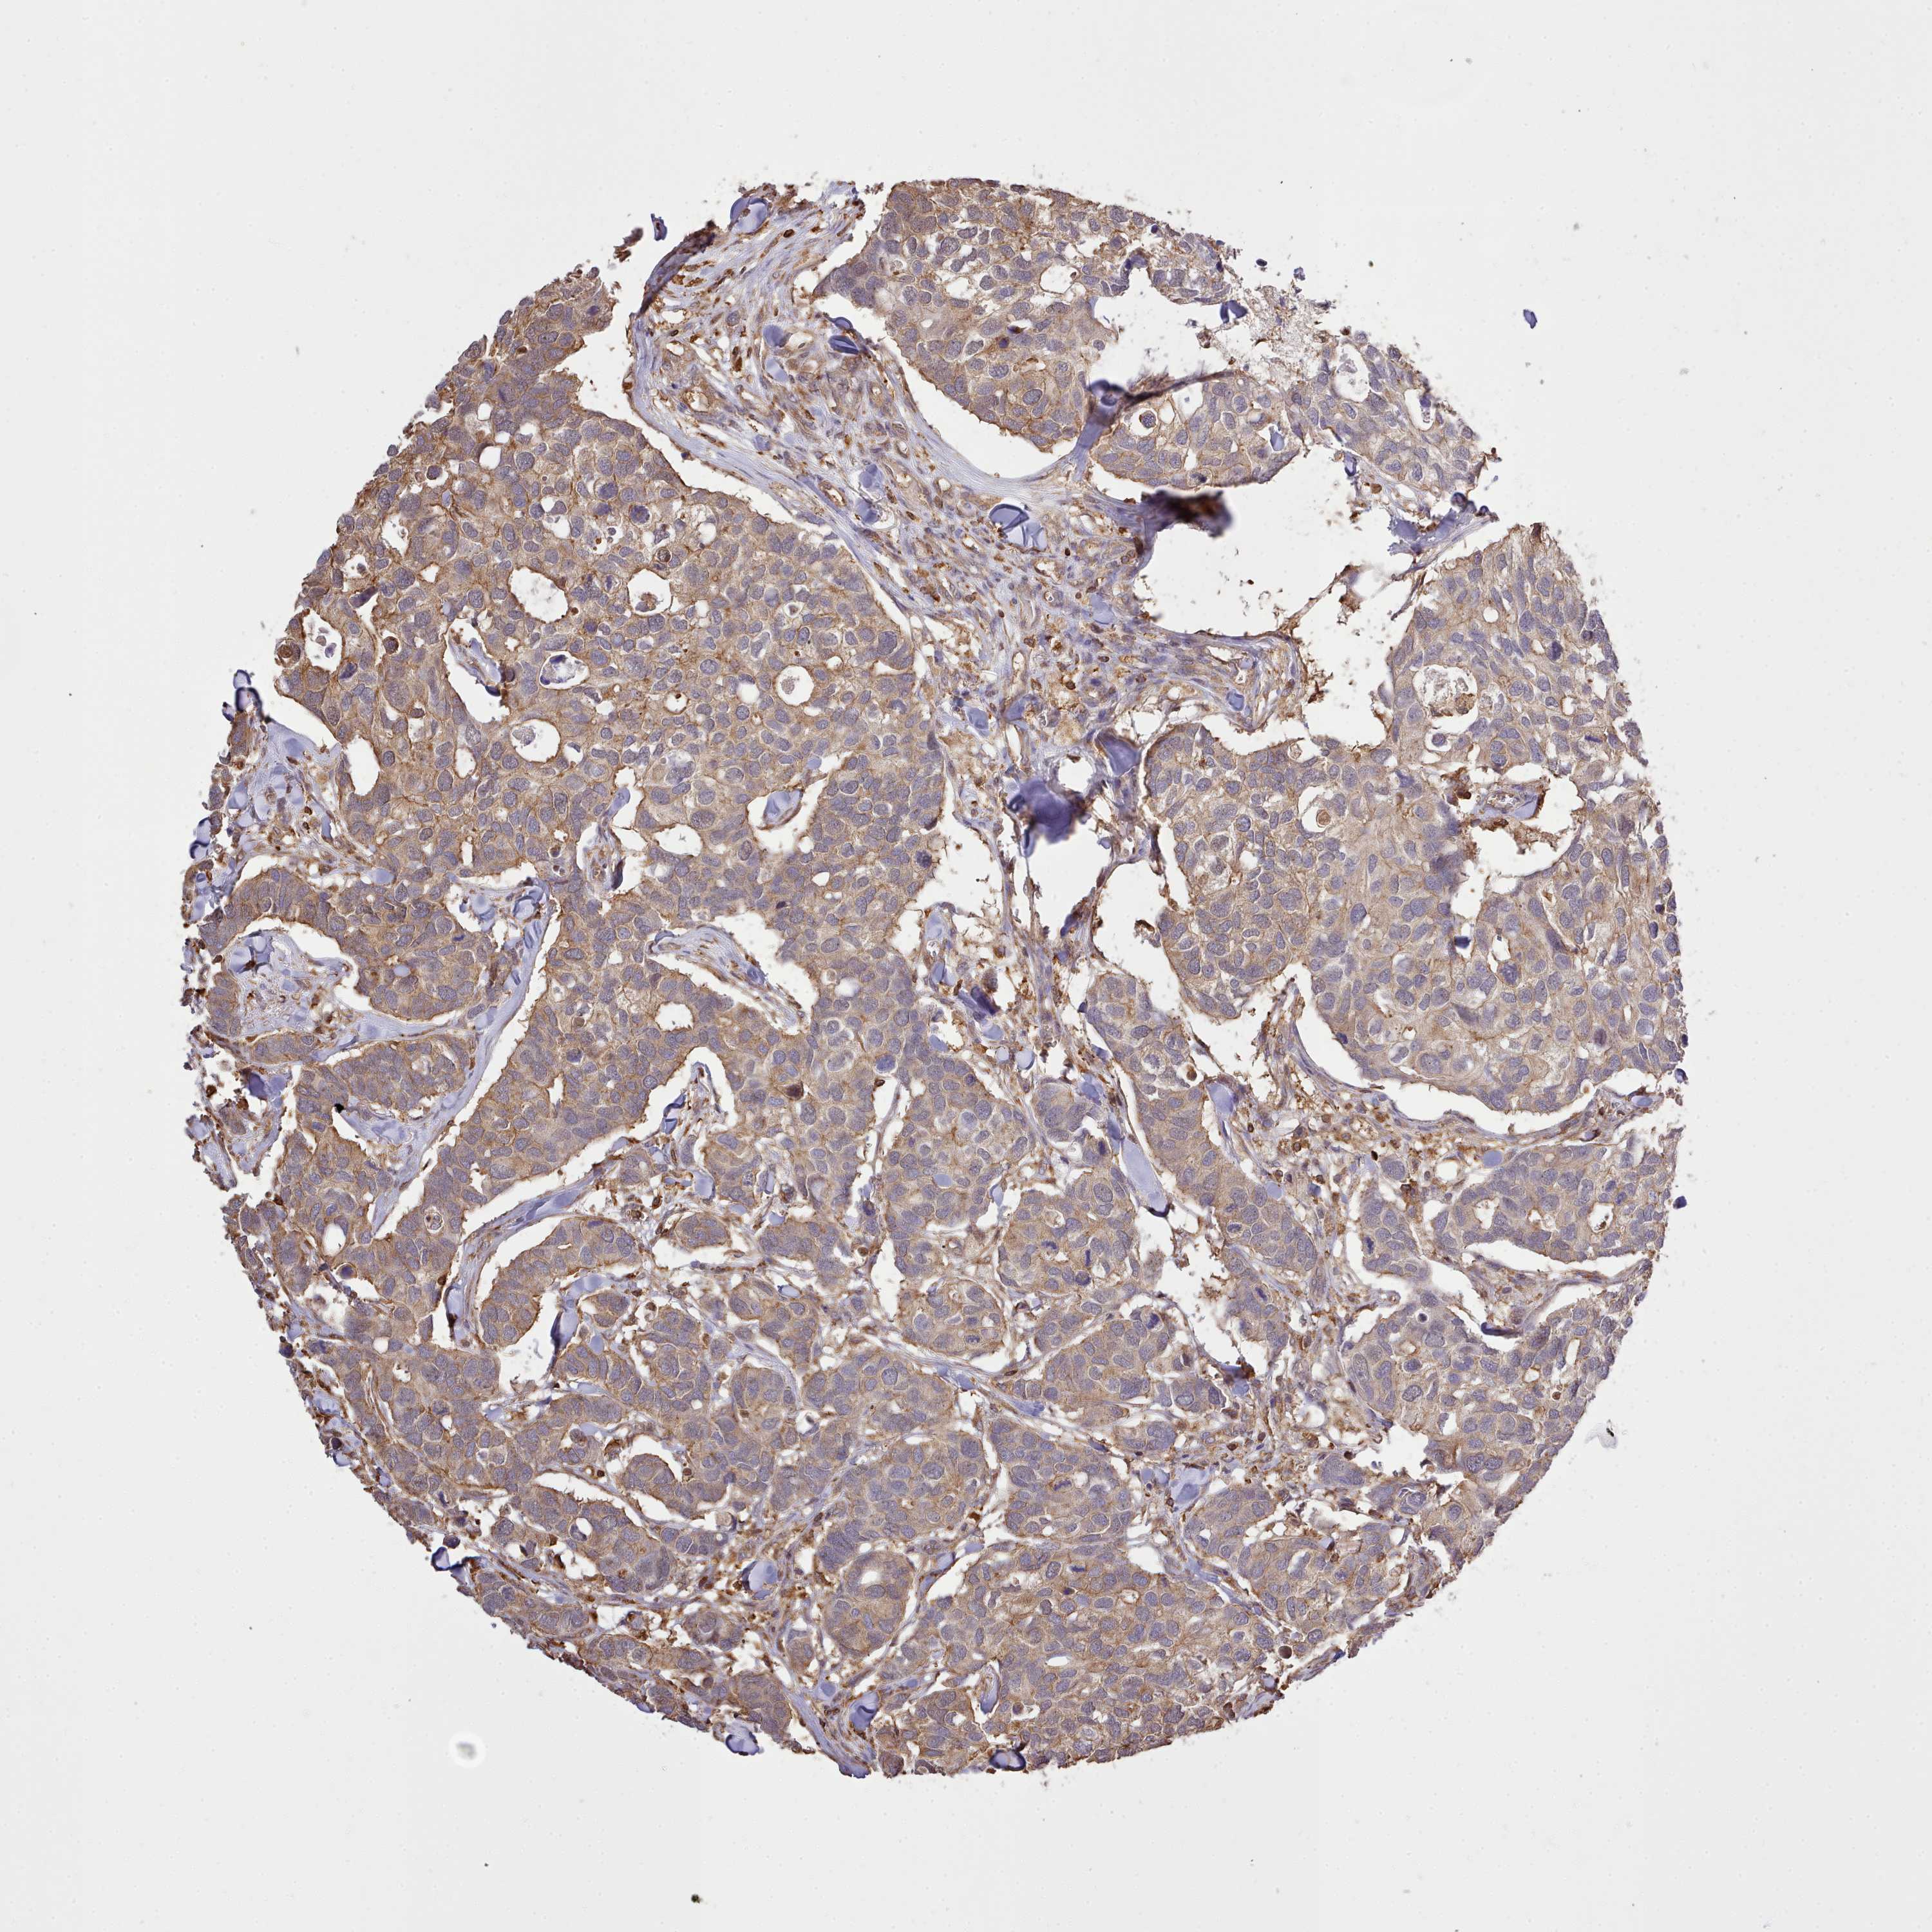

BRCA TCGA BRCA VALIDATION PROTEIN EXPRESSION

Breast cancer

Human cancer

Breast invasive carcinoma